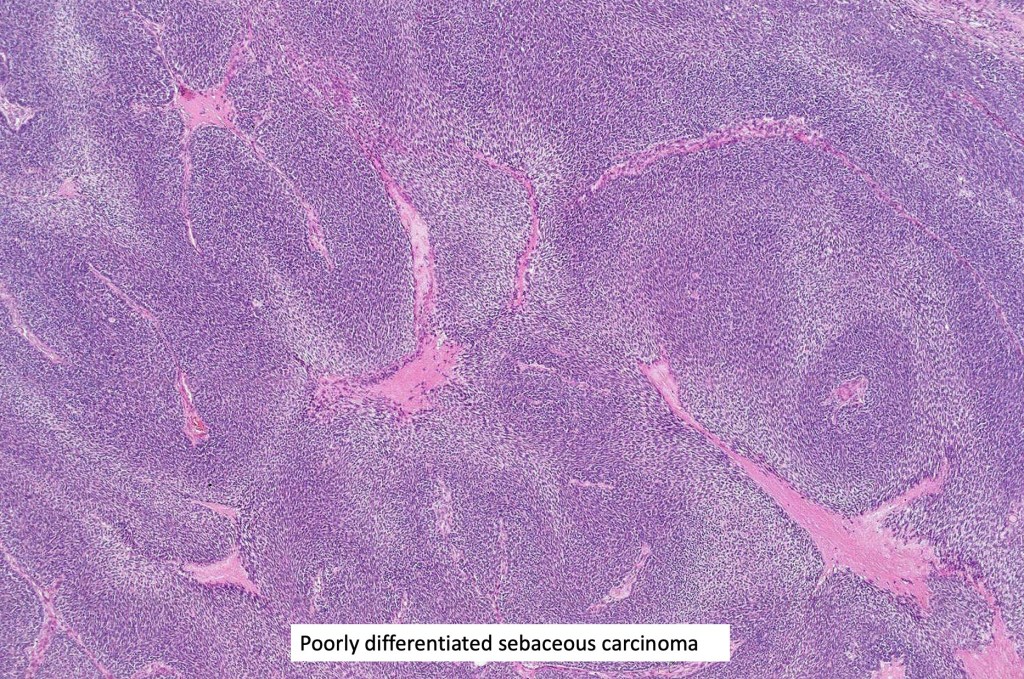

Histological features

•Well differentiated lobular growth pattern though to a poorly differentiated tumor often showing a diffuse, infiltrating border which may extend into the subcutaneous fat

•Peripheral palisading with retraction artifact and mucin deposition as seen in basal cell carcinoma is not present

•Comedo type necrosis commonly present

•Tumors are composed of an admixture of darkly staining basaloid cells with hyperchromatic or vesicular nuclei and more obvious sebaceous cells with eosinophilic, bubbly, multivacuolated cytoplasm frequently indenting the nucleus (scalloped)

•Often mitoses are numerous and abnormal forms evident

•May be graded into well, moderate & poorly differentiated categories. I am not sure that this has any great value

Sebaceous carcinoma from a patient with Muir-Torre syndrome kindly shared by Dr. Antonina Kalmykova.